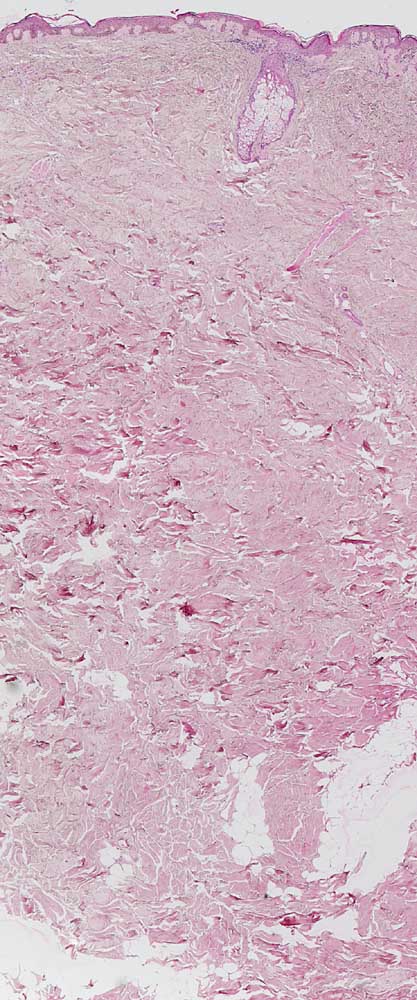

AP/ Chronische Radiodermatitis

Chronische Radiodermatitis

Therapiefolgen

Haut

Haut, Rumpf

Pathologischer Befund